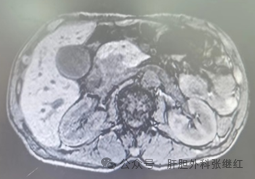

胰腺CT增强一般采用三期扫描:动脉期、胰腺实质期和门脉期。动脉期胰腺实质强化不明显,主要评估肿块周围的重要动脉,胰腺实质期可以获得正常胰腺组织和肿块间的最佳对比度,最后是门脉期,此期正常胰腺实质内造影剂基本退出,如果此期仍可见局灶性强化多数提示为纤维组织的延迟强化,此期也适用于评估肝脏转移。三维动态增强扫描类同于多期增强CT,能清晰显示病灶血供特点以及与周围结构的关系,必要时可以三维成像。

MRI对胰腺肿块的独特优势是软组织对比优于CT。在显示囊液性成分、胰胆管和病灶内出血方面优于CT。脂肪抑制技术减少了相位伪影,增加了胰腺信号强度。磁共振胰胆管成像(magneticresonance cholangiopancreatography,MRCP)显示较小的囊性病变及病变与胰管间的关系方面优于MSCT,它的效能等同于逆行性胰胆管造影(endoscopic retrograde cholangiopancreatography,ERCP)。多种弥散加权成像技术(DWI、IVIM、DKI等),在显示病灶的异质性方面具有较大潜能。

晚期胰腺癌表现为肿块边界不清的低密度改变,可能浸润胰周或包绕胰周血管。局限于胰腺内的癌性肿块表现为边界不清的低密度改变,可致胆管或(和)胰管梗阻性改变。内分泌肿瘤表现为边界较清楚的实性肿块。黏液性和浆液性腺瘤表现为边界清楚的低密度肿块。慢性胰腺炎肿块常伴胰管扩张和结石,甚至胰内潴留性囊肿,糖尿病引起的胰腺炎性肿块在影像学上难与胰腺癌鉴别,但癌抗原19-9(CA 19-9)常不升高或轻度升高。急性胰腺炎后无菌性胰腺坏死表现为胰头低密度灶,但患者近期或近年有急性胰腺炎病史。

对于恶性度较高或有功能的胰腺肿瘤(如PC、功能性PNEN)往往发现时体积较其它胰腺占位直径小。无功能PNEN、SPN、ACCP体积变化较大,可以从数毫米至十几厘米不等,与偶然的影像体检相关,也可能与肿瘤乏嗜神经现象有关。炎性肿块轮廓较光整,无分叶,平扫时与正常组织成等密度或等高混杂密度,钙化多见,成砂粒样或斑片状钙化;动脉期轻度强化(纤维组织增生),病灶呈相对低密度,门静脉期逐渐强化。胰头癌围绕主胰管呈浸润性生长,胰头增大变形,边缘呈分叶状,与正常胰腺分解不清,多成等密度或等低混合密度,液化坏死多见,钙化少见;胰头癌为少血供无包膜实质肿瘤,强化程度弱、速度慢,动脉期表现为不均匀低密度灶,与周围血供丰富的胰腺组织迅速强化形成鲜明对比。

(2)肿块性质:胰腺肿块分为实性、囊性和囊实性肿块,其中有恶性、良性与真性、假性之别。恶性肿块常有坏死液化,密度多有不均匀,轮廓欠规则,增强扫描不均匀强化;良性肿块一般密度均匀,轮廓规整,增强扫描炎性肿块均匀强化。真性囊肿壁薄,影像学上经常不能显示囊壁;一个光滑的壁厚大囊性肿块是假性囊肿的体征。(性质)

(6)血管侵犯:恶性肿瘤侵犯血管或包埋血管;良性肿块不侵犯血管,无包埋血管现象,最多是挤压血管。CT原始横断面薄层图像进行多种三维后处理,显示肿块与周围脏器的空间关系,特别是与周围重要血管之间的关系,能对肿块进行分期和切除性评价,成为胰腺肿块的首选影像方法。(侵血管)